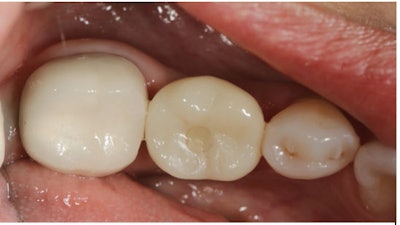

The definitive crown was then designed in CEREC software (Figure 4) using virtual articulation and occlusal analysis (Figure 5) and verified in a full-arch digital view for occlusal harmony (Figure 6). Milling was completed using CEREC Primemill with a Katana Zirconia One for Implant block, producing excellent marginal adaptation and lifelike translucency (Figure 7).

Figure 7: Final milled implant crown design from Katana Zirconia One block (Kuraray).